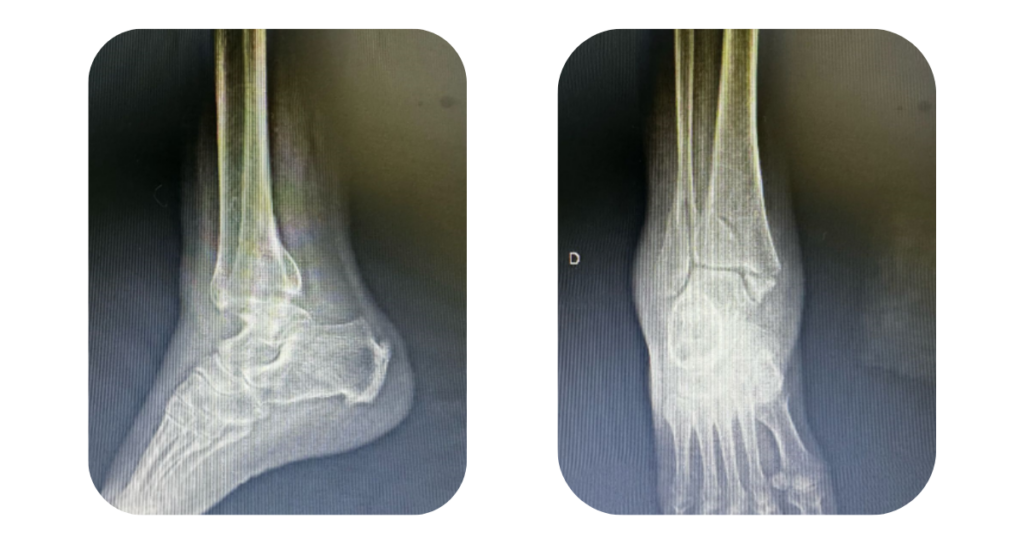

Fraturar o tornozelo é algo que pode acontecer em uma simples torção, queda, acidente ou durante a prática esportiva. Além da dor intensa e do inchaço imediato, uma pergunta comum surge logo após o diagnóstico: “vou precisar de cirurgia?”

Nem todas as fraturas exigem cirurgia. Em casos leves, com osso no lugar e sem instabilidade, o tratamento com imobilização e repouso pode ser suficiente.

Porém, a cirurgia é indicada nos seguintes casos:

• Fraturas com desvio dos fragmentos ósseos

• Fraturas que envolvem dois ou três ossos do tornozelo (bimaleolar ou trimaleolar)

• Quando há deslocamento da articulação (luxação)

• Instabilidade detectada em exames de imagem

• Fraturas que comprometem a função articular ou o movimento

A decisão sempre deve ser tomada por um ortopedista, com base em exames clínicos e radiológicos.